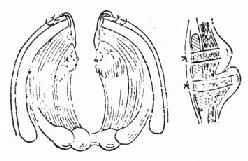

(1)急性声门上损伤:声门上损伤包括甲状软骨板上半部骨折和会厌损伤(图96-1)。有急性喉阻塞者首先行常规气管切开术,然后行前连合直接喉镜检查,注意喉水肿和喉及下咽粘膜裂伤的情况。手术包括缝合粘膜裂口并切除会厌及会厌谿之血肿组织,颈前在舌骨水平做横切口,剪断舌骨后,给行切开甲舌膜进入咽腔(图96-2)。切除会厌,会厌根部血肿组织及双侧假声带(图96-3)。用丝线缝合喉粘膜,尽量对合复位骨折的甲状软骨板,并用丝线缝合甲状软骨外板软骨膜,再缝合甲舌膜(图96-4)。逐层缝合切口。术后48h经鼻咽置入下咽部一条吸引引流管,持续引流。待喉部手术后反应消退,可试行堵管,呼吸道通畅即可拔除气管套管。

图96-1 声门上损伤

图96-2 声门上损伤手术方法 剪断舌骨,纵行切开甲舌膜。

图96-3 切除会厌根部血肿

图96-4 缝合软骨外板软骨膜及甲舌膜